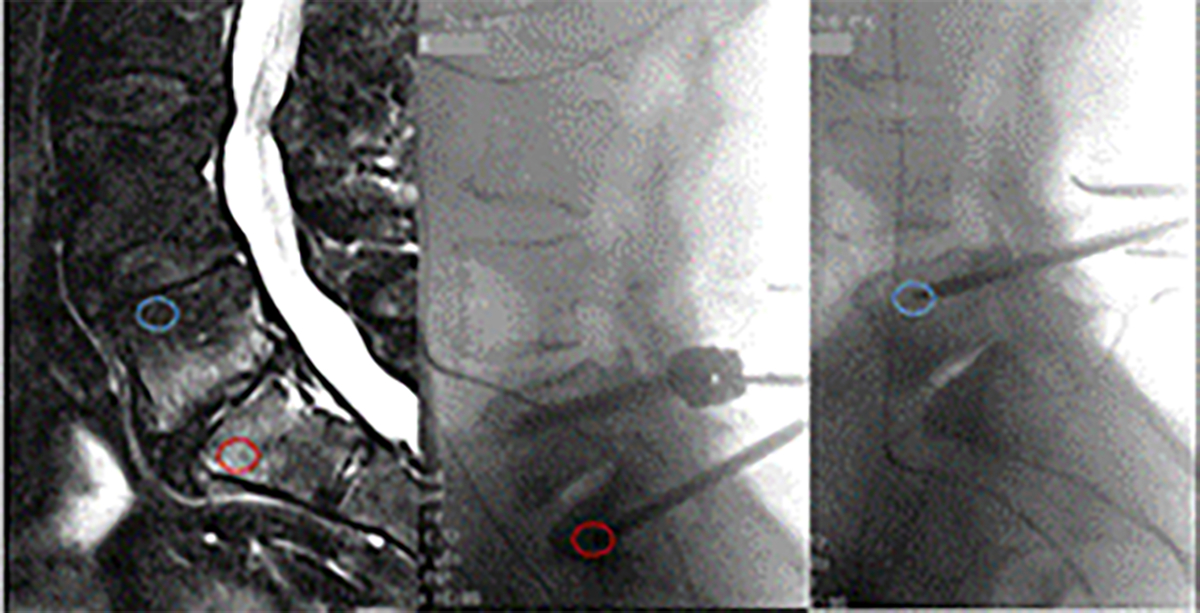

Modic 1型改变(MC1)是一种疼痛的椎体骨髓病变,常见于慢性腰痛患者。骨髓纤维化是MC1的标志。骨髓基质细胞(BMSCs)在其他纤维化骨髓病理中起关键作用,但其在MC1中的作用尚不清楚。本研究旨在表征MC1骨髓间充质干细胞,并假设骨髓间充质干细胞在MC1中的促纤维化作用。骨髓间充质干细胞是从接受腰椎融合术的患者的MC1和邻近对照椎体中分离出来的。比较集落形成单位成纤维细胞(CFU-F)频率、干细胞表面标志物表达、分化能力、转录组、基质粘附性、细胞收缩性以及I型前胶原α 1、α-平滑肌肌动蛋白、整合素和局灶粘附激酶(FAK)的表达。在MC1骨髓间充质干细胞中发现更多的CFU-F和c - x -c基序趋化因子12的表达增加,这可能表明骨髓间充质干细胞人群中有过多的代表性。RNA测序分析显示细胞外基质蛋白和纤维化相关信号基因富集。前胶原I型α 1表达、细胞粘附、细胞收缩性和FAK磷酸化的增加进一步证明了它们的促纤维化表型。此外,瘦素受体高表达(LEPRhigh)的骨髓间充质干细胞群体在转化生长因子- 1刺激下在MC1中分化为肌成纤维细胞,而在对照骨髓间充质干细胞中则没有分化。总之,MC1骨髓间充质干细胞的促纤维化改变和LEPRhigh MC1骨髓间充质干细胞易发生肌成纤维细胞分化。纤维化是MC1的标志,也是潜在的治疗靶点。促纤维化表型和临床特征之间的因果关系有待证实。

Modic type 1 changes (MC1) are painful vertebral bone marrow lesions frequently found in patients suffering from chronic low-back pain. Marrow fibrosis is a hallmark of MC1. Bone marrow stromal cells (BMSCs) are key players in other fibrotic bone marrow pathologies, yet their role in MC1 is unknown. The present study aimed to characterise MC1 BMSCs and hypothesised a pro-fibrotic role of BMSCs in MC1. BMSCs were isolated from patients undergoing lumbar spinal fusion from MC1 and adjacent control vertebrae. Frequency of colony-forming unit fibroblast (CFU-F), expression of stem cell surface markers, differentiation capacity, transcriptome, matrix adhesion, cell contractility as well as expression of pro-collagen type I alpha 1, α-smooth muscle actin, integrins and focal adhesion kinase (FAK) were compared. More CFU-F and increased expression of C-X-C-motif-chemokine 12 were found in MC1 BMSCs, possibly indicating overrepresentation of a perisinusoidal BMSC population. RNA sequencing analysis showed enrichment in extracellular matrix proteins and fibrosis-related signalling genes. Increases in pro-collagen type I alpha 1 expression, cell adhesion, cell contractility and phosphorylation of FAK provided further evidence for their pro-fibrotic phenotype. Moreover, a leptin receptor high expressing (LEPRhigh) BMSC population was identified that differentiated under transforming growth factor beta 1 stimulation into myofibroblasts in MC1 but not in control BMSCs. In conclusion, pro-fibrotic changes in MC1 BMSCs and a LEPRhigh MC1 BMSC subpopulation susceptible to myofibroblast differentiation were found. Fibrosis is a hallmark of MC1 and a potential therapeutic target. A causal link between the pro-fibrotic phenotype and clinical characteristics needs to be demonstrated.